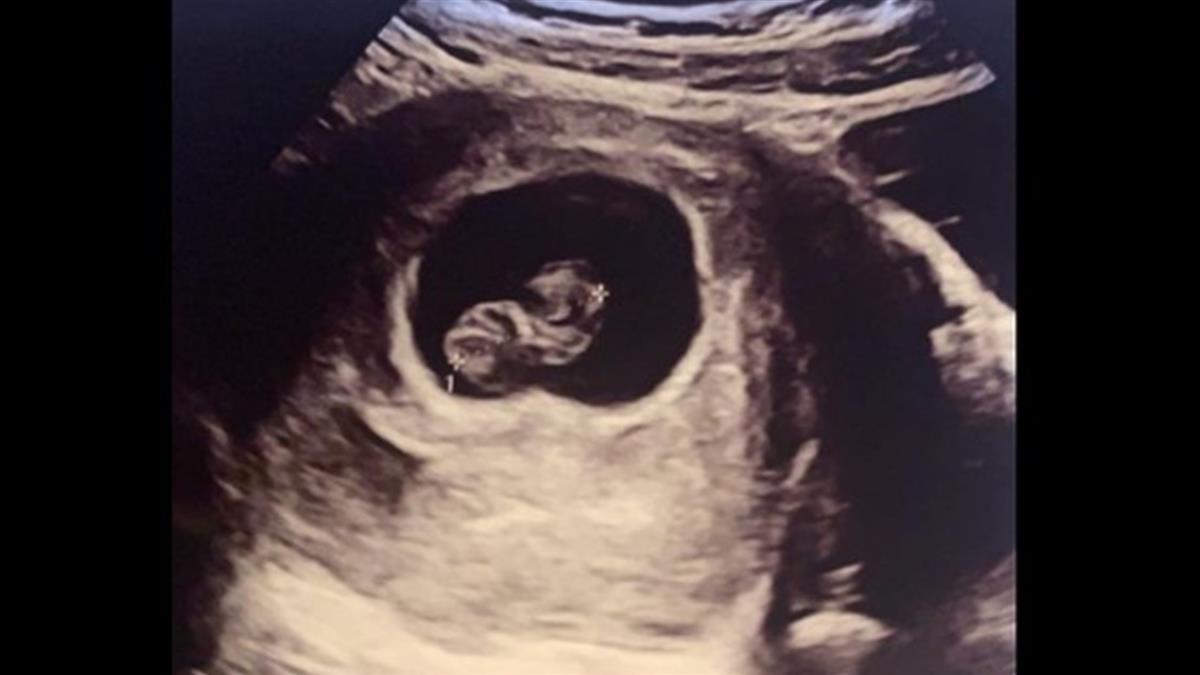

有名女性網友今(13日)在臉書「靠北男友/老公」社團貼文發表,她現在懷孕8週,去醫院定期檢查時,發現胚胎發育不完全,寶寶已經沒有心跳,儘管心裡仍舊抱持著一絲希望,但再次回診時,醫師告訴她「胚胎已經水腫,絕對留不住了」,她也很冷靜地問該如何處置,並安排下次動手術的時間。

▼一名女網友在臉書靠北男友/老公社團發文分享她最近發生的事情。(圖/翻攝自臉書靠北男友/老公社團)

(封面圖/翻攝自臉書靠北男友/老公社團)